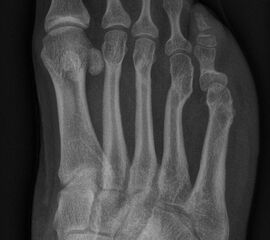

In der Regel bestehen aktive Wachstumsfugen bei Mädchen bis zum 12. und bei Jungen bis zum 14. Lebensjahr, mit Abweichungen von einem Jahr nach unten und nach oben. Präzise Informationen unter anderem darüber gibt das präoperative Röntgenbild (Abb. 2).

Abb. 2 a-c: offene Wachstumsfugen MT I Basis und Zehen (a), teilweise geöffnete Wachstumsfugen (b) und geschlossene Wachstumsfugen (c).

Zum Lesen der Bildbeschreibung und zur Vollansicht bitte die Bilder anklicken. Bilder: A. Helmers.